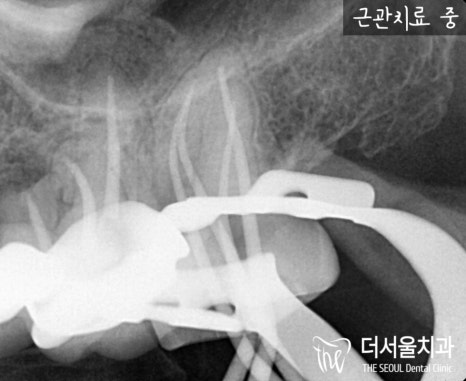

우선 신경치료는 감염된 치수를 싹 다 제거합니다.

조금이라도 남아있게 된다면,

언제든 재발하여 다시 썩게 되는데요.

그런 상황이 발생해버리면,

다시 내원하셨을때

판교치과 에서 이를 발치하게 될 수 있습니다.

그정도로 좋지 않은 예후가 찾아올 수 있으므로

꼼꼼히 체크하여 감염된 치수를 처리하고

속을 깨끗하게 소독해줍니다.

그 후, 텅 빈 근관을 충전 재료로

채워넣어 튼튼히 만들어줍니다.